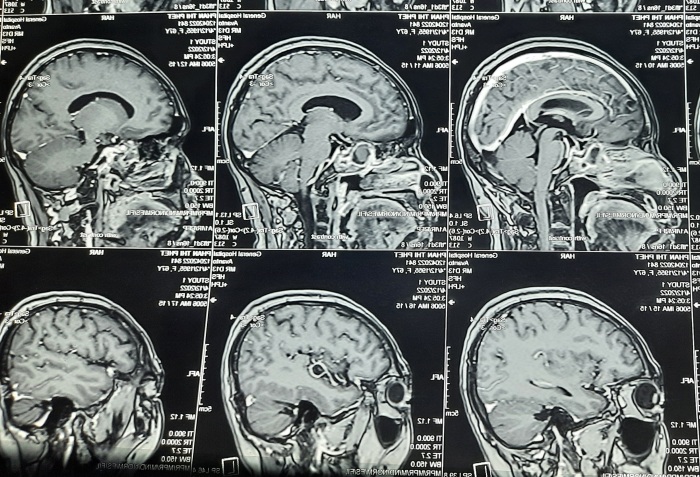

Hình ảnh MRI